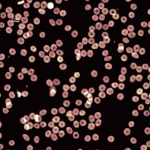

The Digital Holographic Camera 5 Mpixels camera provides a 4X larger field of view compared to standard imaging devices with a higher spatial and temporal resolution. Thus allowing to quantify fine and fast changes occurring in your sample in a completely non-invasive way.